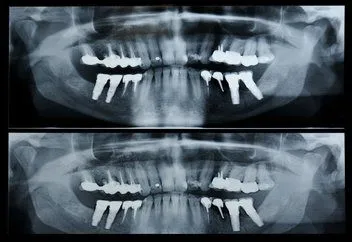

Pan_x_ray.jpg A panorex is a very impressive piece of imaging machinery in that it is capable of identifying many issues and structures that a normal x-ray is not. Initially you will sit in a chair with your chin on a small ledge. Once positioned in the machine, it will rotate around your entire head taking a full 360 degree view of the teeth, head, sinuses and bones.

The ability to view the full structure of your head as a whole is very informative to the dentist. It will allow us to see any potential problems and make sure that everything is functioning as it should be. The panorex is capable of viewing specific types of structural problems, infections or asymmetry among many others.